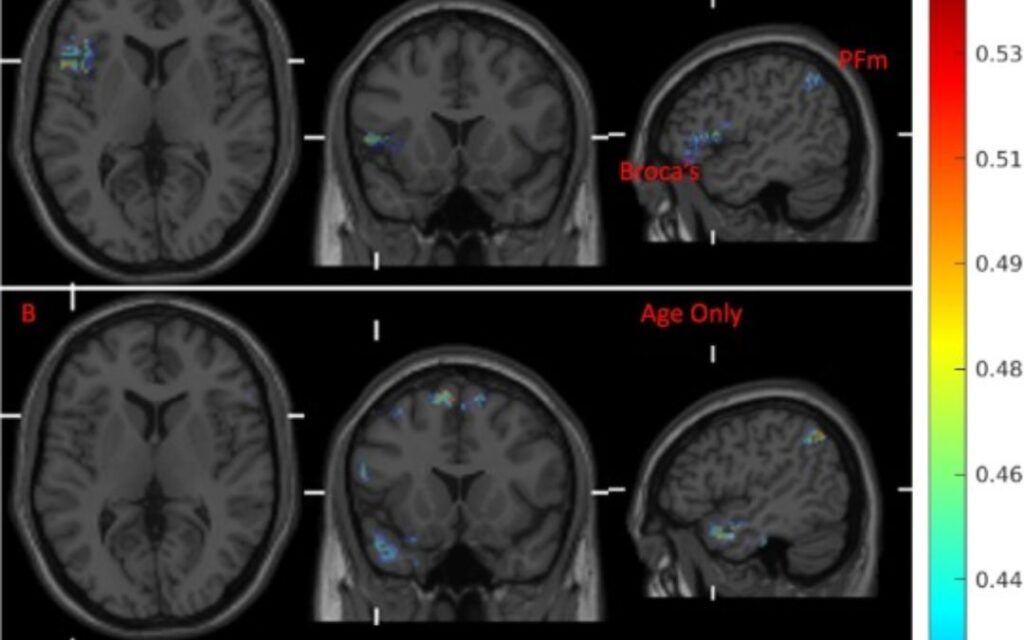

Research Altered functional connectivity strength between structurally and functionally affected brain regions in visual snow syndrome